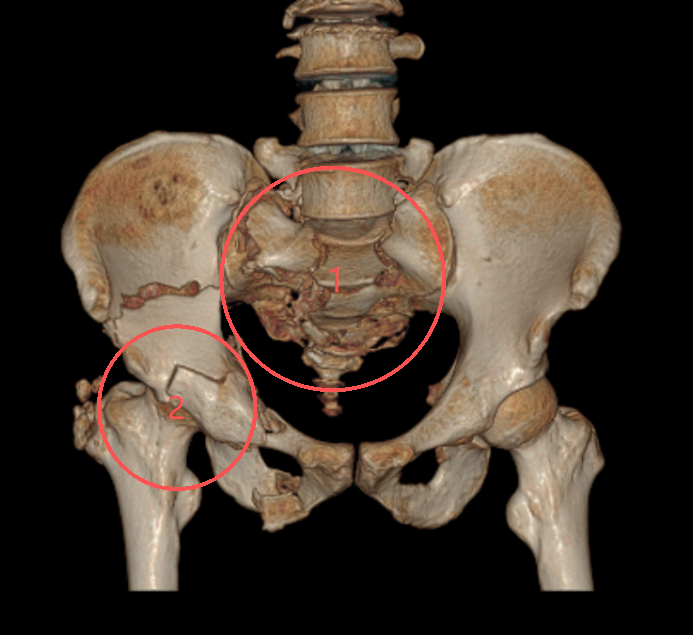

严重骨盆骨折,骶骨粉碎H型骨折,右侧髋臼骨折。图中“1”为骨盆后环骶骨严重粉碎性骨折,预示着高能量损伤,往往见于高处坠落伤,会引起致命性大出血和神经损伤;图中“2”为髋臼双柱骨折,治疗难度大,被称为创伤骨科的“皇冠级”手术。时间就是生命!急诊外科团队立即启动严重创伤救治预案,准备实施损伤控制手术——以简单有效的外固定,快速控制出血、稳定骨盆环和肢体力线,稳定血液动力学,逆转“死亡三联征”,为抢救生命创造机会。